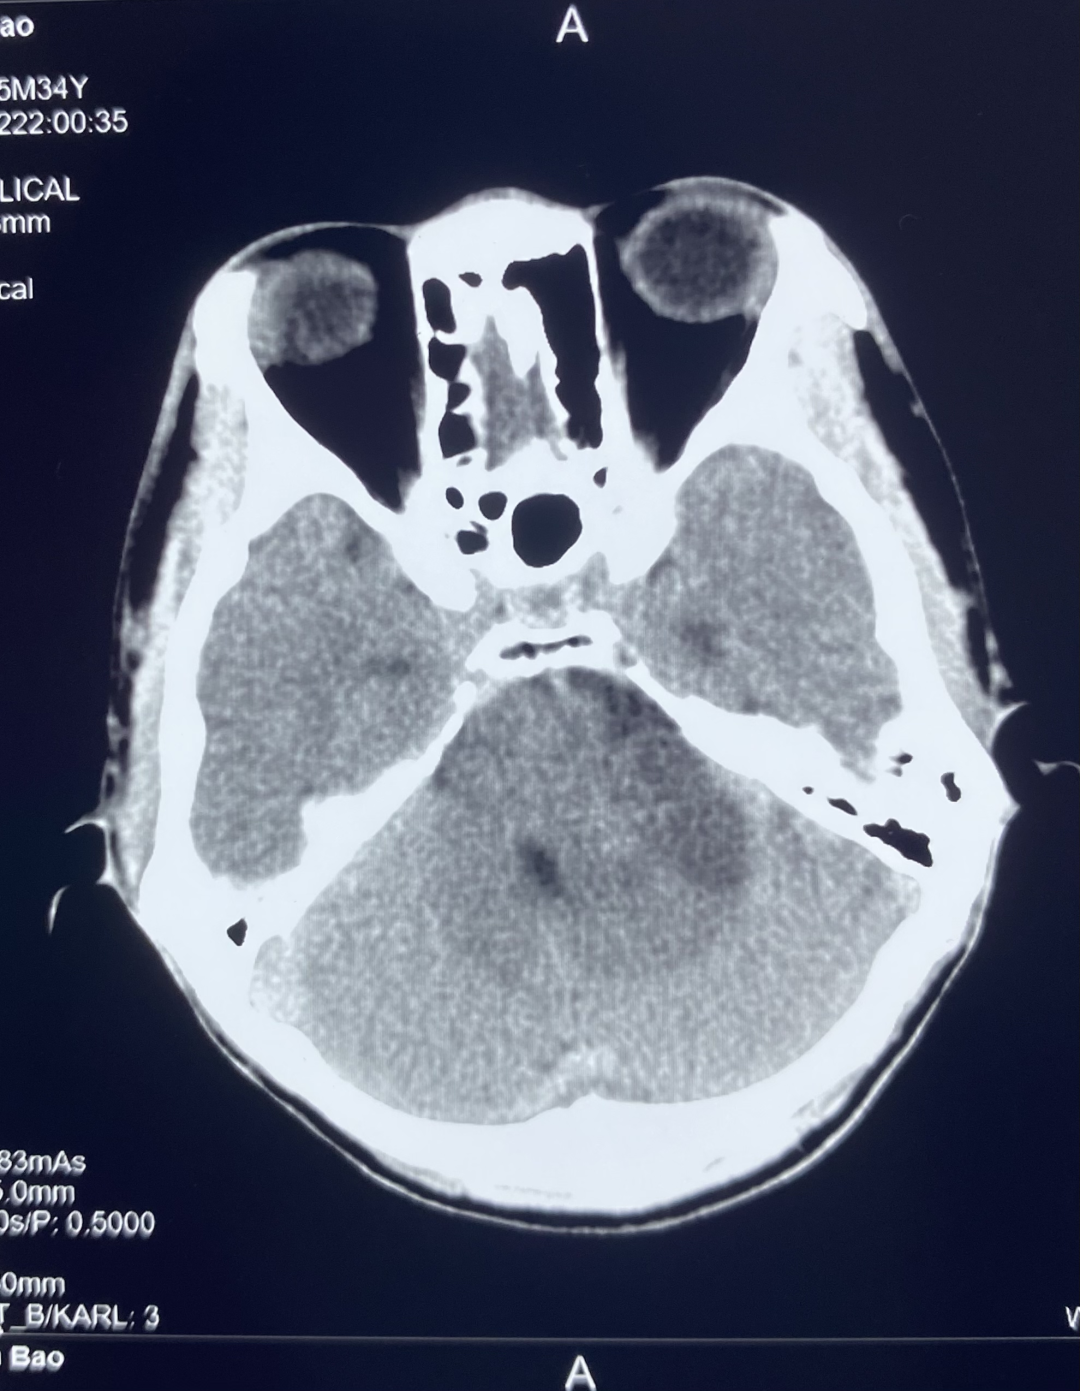

1、颅脑 CT 平扫

颅脑 CT 平扫显示左侧桥小脑角区可见团块状异常密度,大小约 3.0*3.4 cm,边界不清,内部密度欠均匀,可见低密度坏死区,左侧内听道较对侧扩大,邻近小脑受压。

诊断:左侧桥小脑角区占位,建议进一步检查。